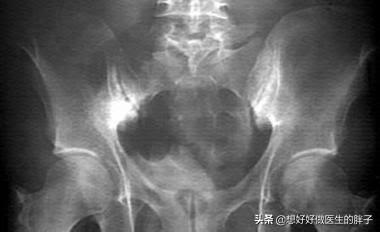

强直性脊柱炎属于风湿免疫科的疾病。具体的原因到现在也不是非常的明确。这种疾病主要累及骶髂关节、脊柱以及一些大的关节。病变的部位会发生比较严重的纤维化、骨化。患者出现疼痛以及日渐加重的活动受限。

强直性脊柱炎中晚期脊柱活动受限。检查x线可以发现典型的竹节样改变。诊断往往不难。早期诊断却容易和腰疼混淆。导致遗漏。早期的强直性脊柱炎患者以下的一些特点:

其实很多强直性脊柱炎的患者往往并不知道自己得了这个病。多数到医院就诊是因为下背部的疼痛、腰痛以及骶髂关节部位的疼痛。如果一个患者有明显的骶髂关节的疼痛。而且年龄比较轻。那么医生要予以重视。最好要咨询一下是否有晨起明显疼痛加重的情况。是否有家族性强直性脊柱炎的病史。而且要秉着宁可错杀1000。不能放过一个的原则。要给予患者进行下列这些检查:

强直性脊柱炎是一种严重危害人类健康的风湿免疫性疾病。是一种是以骶髂关节和脊柱附着点炎症为主要症状的疾病。主要影响脊柱、胸腔和骨盆的关节。这几处的关节会生长粘连在一起。时间长了。脊柱就会失去灵活性。